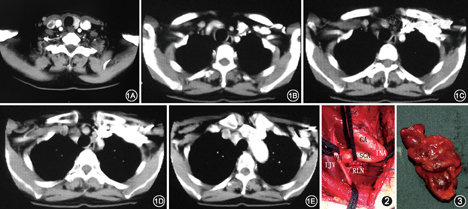

入院后体格检查:一般状况好,生命体征平稳。颈软无抵抗,颈静脉怒张,颈动脉无异常波动,气管居中,颈部可见横行手术瘢痕。甲状腺未触及明显肿物,右侧下颈部可及明显肿大淋巴结,大小2.0 cm×2.0 cm,质地硬,边界不清,较固定。喉镜检查结果示:右侧声带旁正中位固定。实验室检查:甲状腺功能、甲状旁腺素均正常;血清降钙素879.0 ng/L(正常值0~5.0 ng/L);癌胚抗原126.0 mg/L(正常值0~5.0 mg/L)。甲状腺B超结果显示:甲状腺右叶术后缺如,术区未见占位;左叶见数个低回声小结节,最大径约0.3 cm,界清,未见明确血流;右下颈见低回声结节,大小2.0 cm×1.5 cm,界清,内见强回声光点,可探及丰富血流;左侧中上颈见多发条状淋巴结,大小2.2 cm×0.6 cm,可见淋巴结门,可探及中心血流;余双颈未见明确肿大淋巴结。超声诊断:甲状腺右叶术后;甲状腺左叶结节,倾向良性;右下颈淋巴结肿大,转移可能大;左侧中上颈淋巴结探及。CT扫描结果示:甲状腺右叶及峡部缺如,术区可见略低密度影,倾向术后改变;右侧颈深组淋巴结及上纵隔可见多发肿大淋巴结,强化较明显,较大者大小约2.0 cm×1.2 cm,考虑甲状腺癌淋巴结转移(图1)。入院诊断:甲状腺髓样癌外院术后,右颈及右上纵隔淋巴结转移,右喉返神经麻痹。

完善术前准备,于2014年3月5日全身麻醉下,按原手术切口,沿皮纹向右延伸至右斜方肌前缘,颈阔肌下翻起皮瓣,行保留胸锁乳突肌、颈内静脉和副神经的Ⅱ~Ⅴ区清扫;解剖左喉返神经,保护左侧上下甲状旁腺后,行甲状腺左叶切除;解剖出右颈总动脉、颈内静脉、右锁骨下动脉、无名动脉和右无名静脉,经颈部将气管前及右上纵隔淋巴脂肪组织整块切除,完成经颈部右上纵隔清扫(图2,图3)。术后病理学检查结果:淋巴结转移性甲状腺髓样癌;淋巴结转移7/44,部分累及淋巴结被膜外,右颈Ⅱa区淋巴结2/5,右颈Ⅱb区淋巴结0/6,右颈Ⅲ区淋巴结4/14,右颈Ⅳ区淋巴结0/2,右颈Ⅴ区淋巴结0/15,上纵隔淋巴结1/2;免疫组化:癌胚抗原(+++),Syn(+++),CD56(+++),TT1(+++),甲状腺球蛋白(–);甲状腺左叶:结节性甲状腺肿;气管前清扫:术后改变,未见癌。